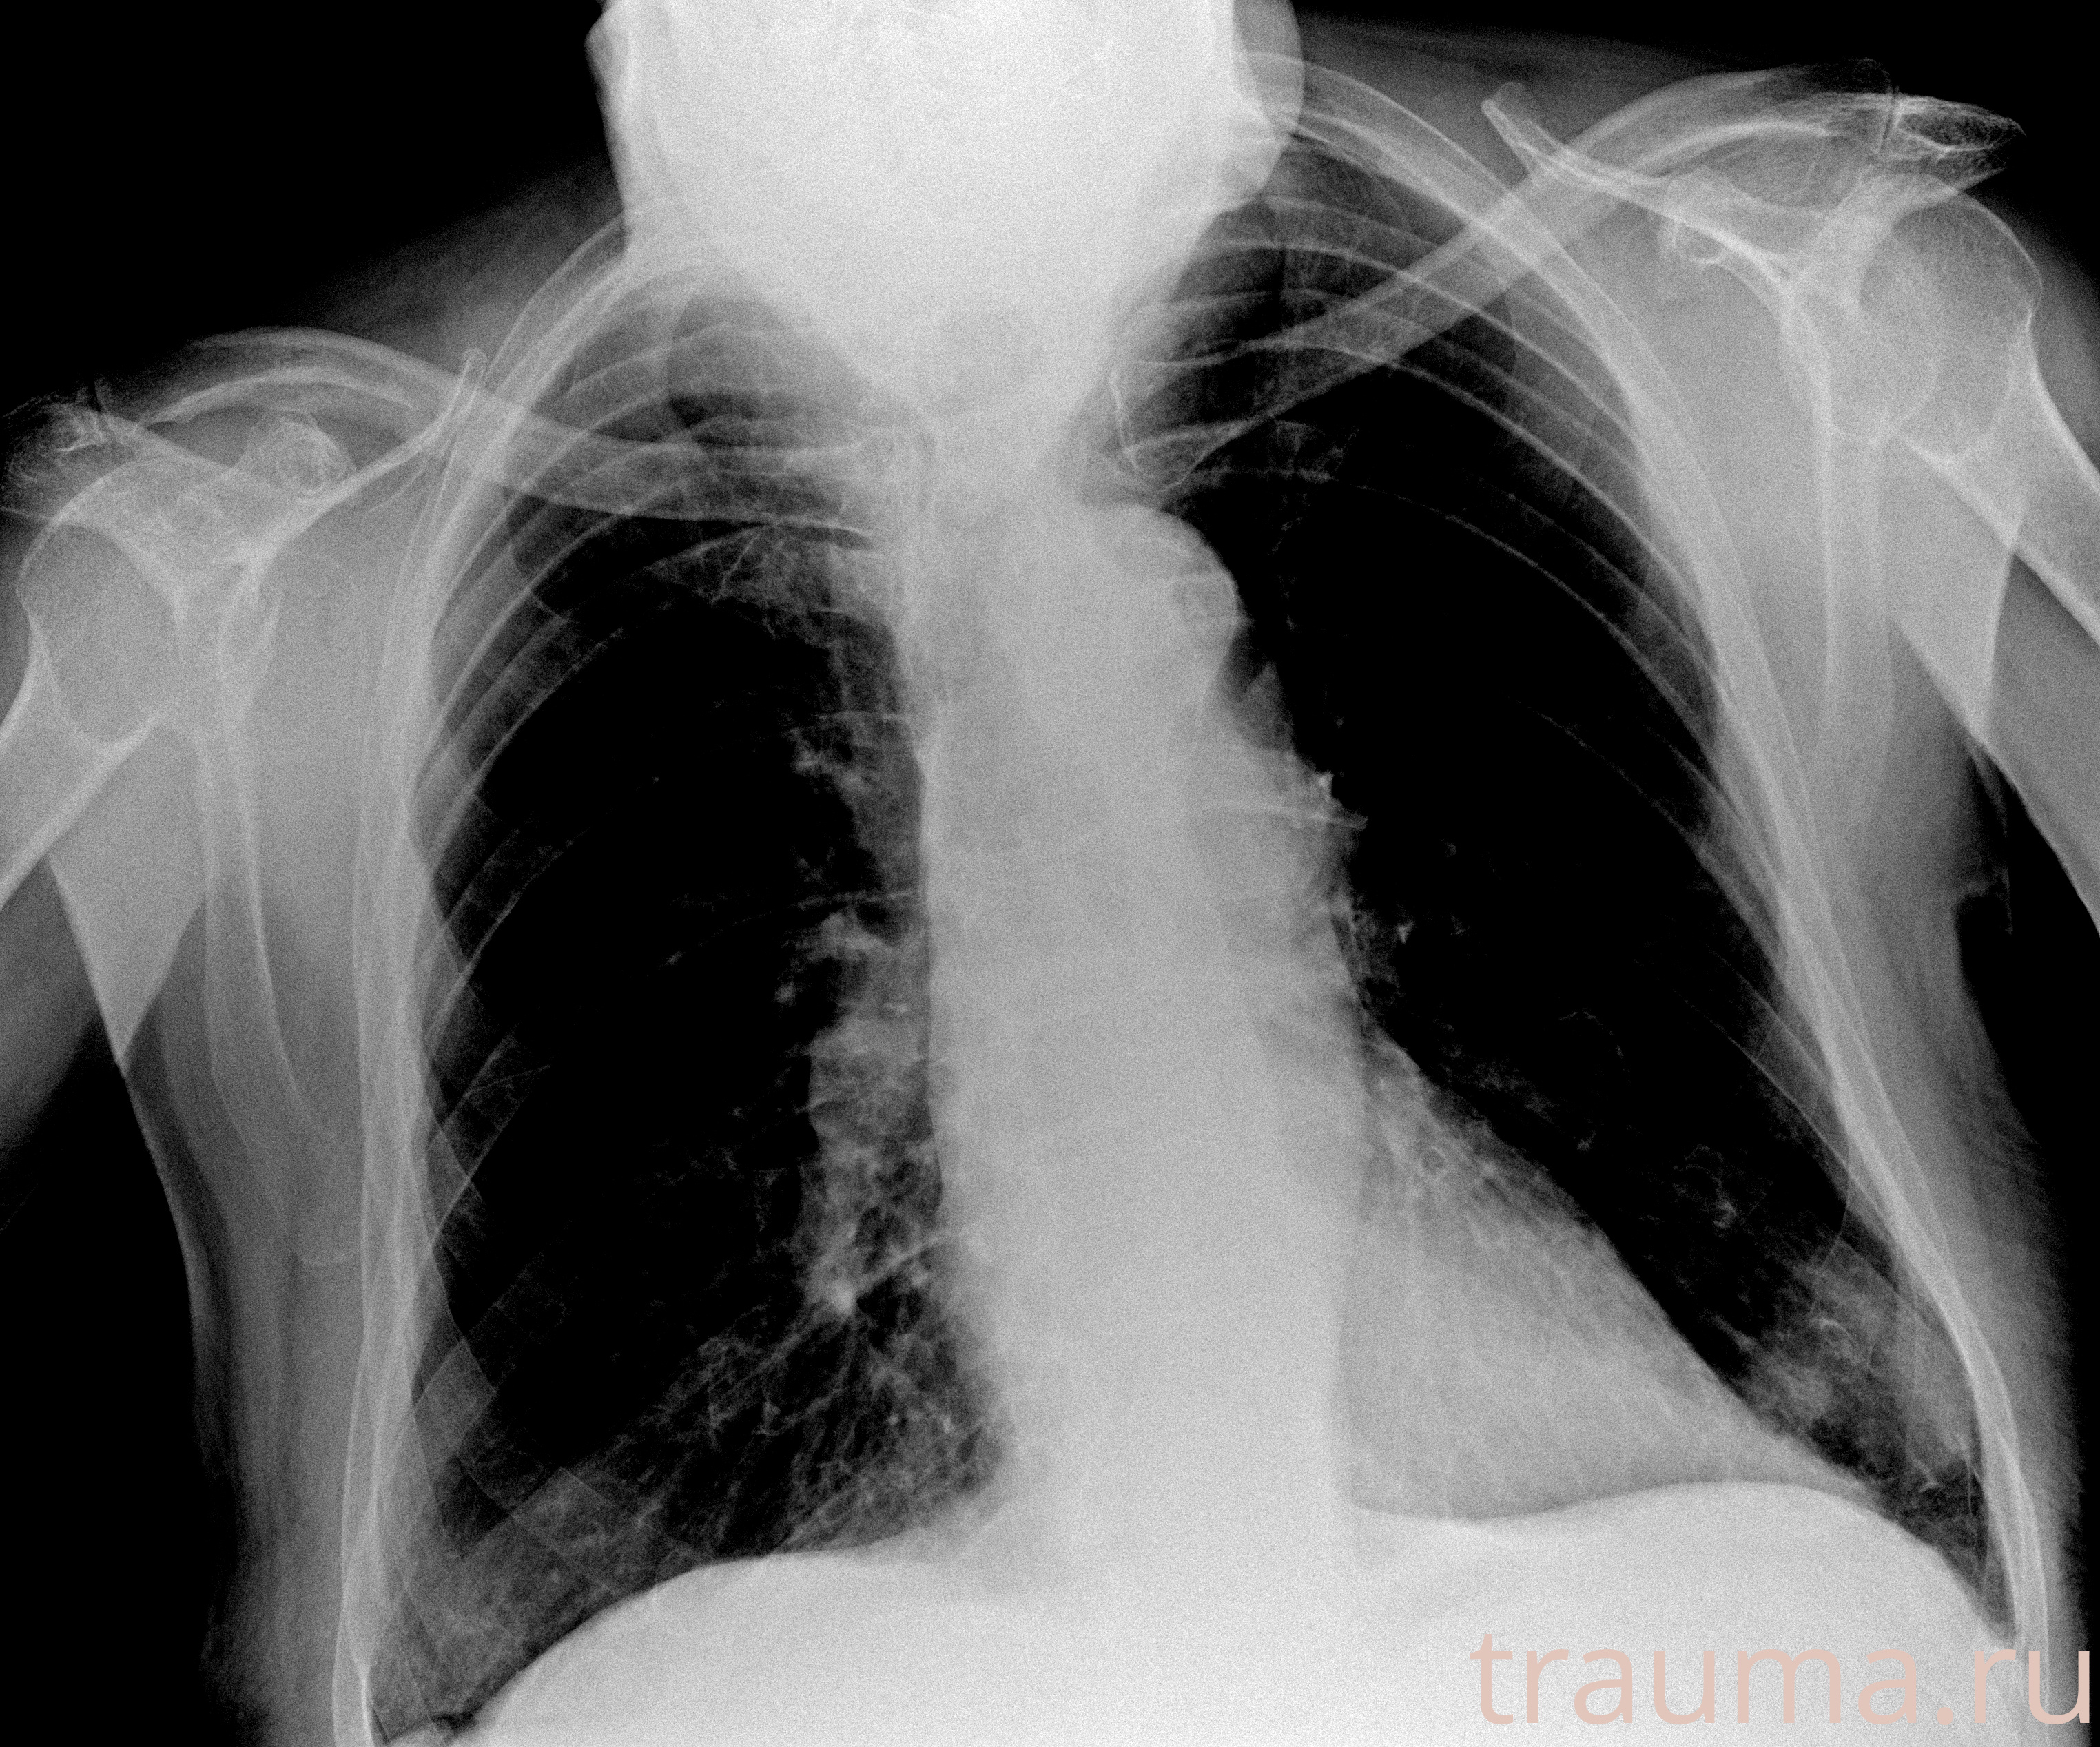

Рентгенограммы

Рентген на дому: по вашему адресу приезжает врач-рентгенолог, травматолог-ортопед с мобильным рентгеновским аппаратом, проводит диагностику травмы или заболевания, делает необходимые рентгенограммы, дает рекомендации по дальнейшему лечению. Получить качественные снимки в домашних условиях возможно благодаря уникальной методике, разработанной МосРентген Центром для института  Склифосовского